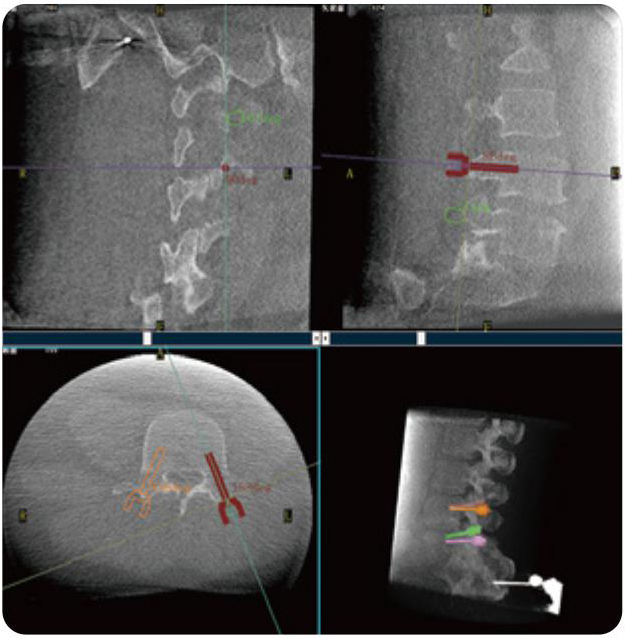

PL300B可應(yīng)用于多節(jié)段脊柱外科手術(shù),輔助醫(yī)生定位病灶部位,為脊柱外科手術(shù)(經(jīng)皮椎體成形術(shù)、椎弓根螺釘內(nèi)固定術(shù)等術(shù)式)提供術(shù)前手術(shù)流程規(guī)劃、入釘位置、角度可視化引導(dǎo),模擬仿真入釘輔助。

PL300B搭配普愛醫(yī)療自主研發(fā)生產(chǎn)的平板3D C形臂,借助一體化自適應(yīng)配準(zhǔn)( 軌跡配準(zhǔn))技術(shù),通過追蹤C(jī)形臂三維采集軌跡,自動完成圖像坐標(biāo)建立和系統(tǒng)坐標(biāo)配準(zhǔn)。配準(zhǔn)精度更高,操作步驟少,系統(tǒng)運(yùn)作效率高。